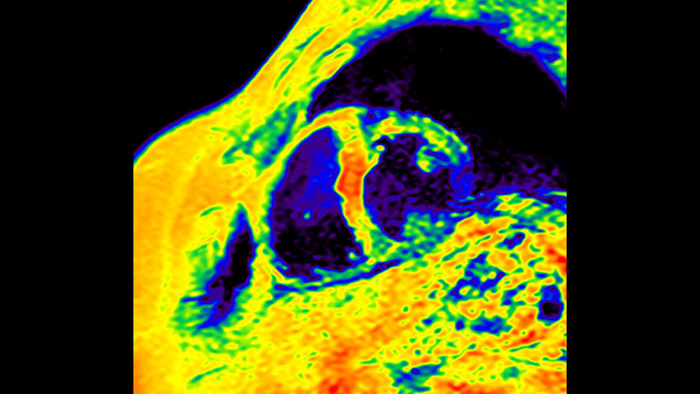

IntelliSpace Portal MR Caas5,6 Strain7 assists in patient diagnosis and monitoring by providing global strain parameters such as global longitudinal strain (GLS), global circumferential strain (GCS), and global radial strain (GRS), using short and long axis MR images, as well as describing the myocardium deformation- such as shortening, thickening, and lengthening during the cardiac cycle.